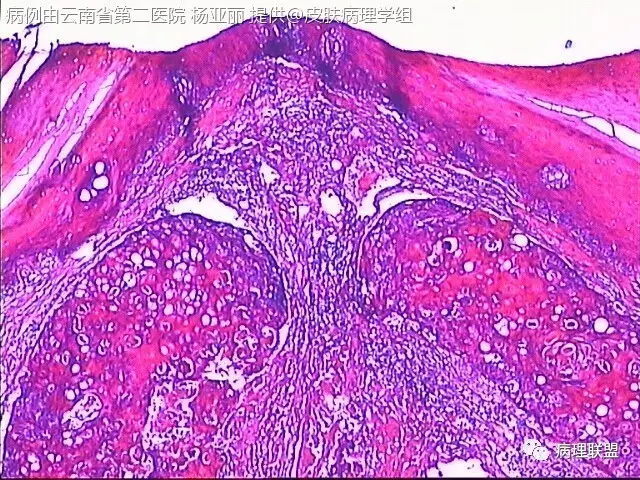

M/53 左手食指包块(皮肤鳞癌VS转移性鳞癌)

请各位老师帮忙看看,男性,53岁,左手食指包块 (病例由云南省第二医院 杨亚丽 提供,致谢!)

@邓永键 谢谢邓主任,据说病人鼻子上有肿瘤才来切的手上的小包块,右手有,左手也有三四个,等我再问问鼻子上的是什么。看着细胞异型不明显,生长方式倒是确实不好。第6图有和表皮的关系,不相连,邓老师,鼻子上的肿瘤确实是鳞癌,这么说来手上的是转移的就很合理了。邓主任真是高,佩服!